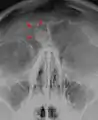

Osteoma represents the most common benign neoplasm of the nose and paranasal sinuses. The cause of osteomas is uncertain, but commonly accepted theories propose embryologic, traumatic, or infectious causes. Osteomas are also found in Gardner's syndrome. Larger craniofacial osteomas may cause facial pain, headache, and infection due to obstructed nasofrontal ducts. Often, craniofacial osteoma presents itself through ocular signs and symptoms (such as proptosis).[2]